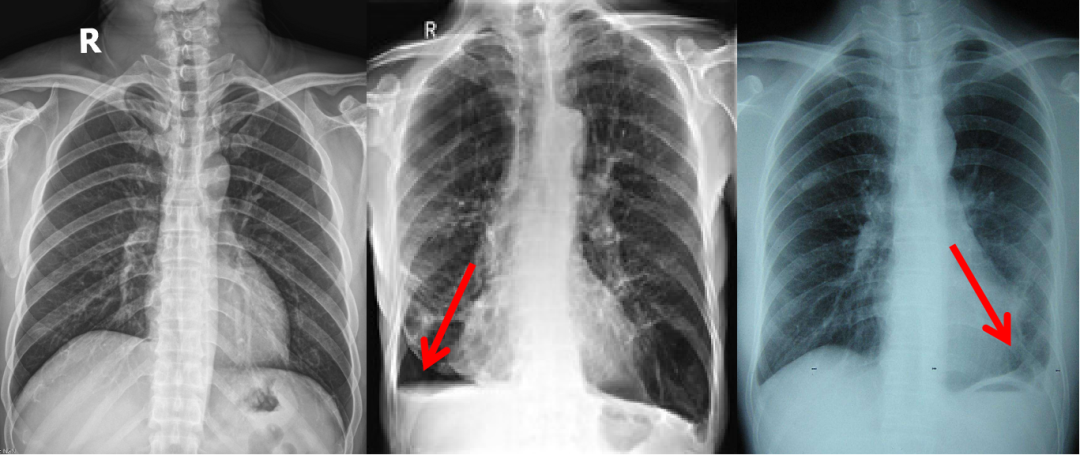

左图正常,双侧肋膈角锐利;中图右侧肋膈角变钝,少量胸腔积液;右图左侧胸膜粘连,肋膈角消失。

少量胸腔积液:如果胸腔积液量不多,因重力作用,首先聚集在最低处,也就是肋膈角处,在X线正位片上就会表现为肋膈角变钝,这是最常见的原因。当然,也可以是胸腔积血等。进一步讲,如果胸腔积液量超过300ml时,肋膈角就不是变钝了,而是肋膈角消失,甚至整个下肺野实变。

胸膜粘连:胸膜炎,胸膜粘连、胸膜增厚时,也可以将肋膈角封闭,表现为肋膈角变钝。